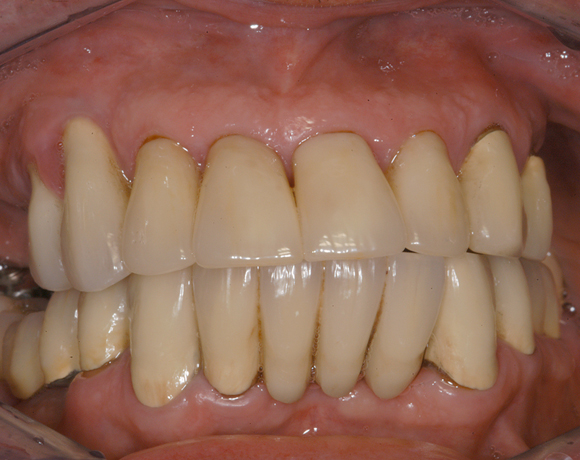

Im vorliegenden Patientenfall musste eine komplette Neukonstruktion der Oberkieferversorgung vorgenommen werden, da auf Grund parodontaler Probleme die Seitenzahnbrücken 15 – 17 und 25 – 27 nicht mehr zu halten waren. Die verbliebenen acht Frontzähne bzw. Prämolaren waren auch parodontal vorgeschädigt und es war ungewiss wie lange sie einzelne noch halten lassen. Um nicht bei jedem Verlust eines der Restzähne eine Neukonstruktion zu brauchen, hat man sich für eine Teleskopprothese entschieden. Für den Patienten war es allerdings nicht vorstellbar goldfarbene Primärteile im Mund zu haben, so wurde der Versuch unternommen diese aus e.max Press und Galvano Sekundärteilen herzustellen.